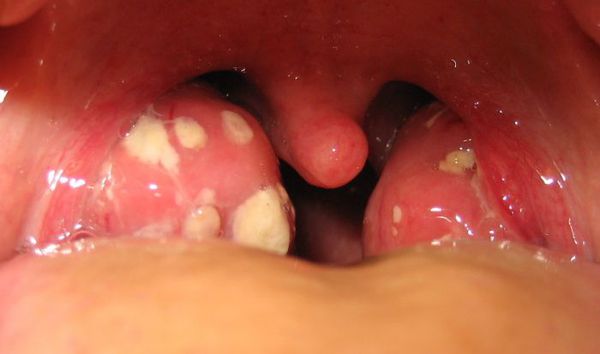

- фолікулярна (фолікули білого кольору тканини мигдаликів);

- лакунарна (гнійне виділення з лакун мигдаликів);

Мигдалики набряклі, червоного кольору («соковиті»), що відповідає катарального тонзиллиту. Зазвичай цю стадію захворювання не розпізнають (не встигають) і яскрава візуалізація настає на другу добу захворювання, коли в тканини мигдалин утворюються фолікули білого кольору, розмірами 2-3 мм, що підносяться над поверхнею тканини мигдалин — розвивається фолікулярний тонзиліт.

З третього дня в лакунах з’являється виділення жовто-білого кольору (гній) — фолликулярно-лакунарный тонзиліт.

- Фолікулярна ангіна – поразка відбувається в фолікулярній частини мигдалини. Самі органи також набряклі, збільшені в розмірах, крізь поверхневий покрив епітелію фолікулів добре проглядаються гнійні запальні вогнища. Як правило, вони блідо-жовтого кольору, можливі рожеві кров’яні домішки. Збудниками виступають також пневмококи і стафілококи.